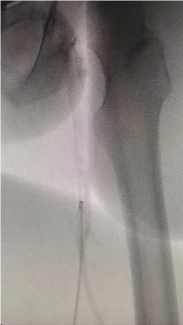

Basavanna Dinesh, MD, DM; Yamasandi Siddegowda Shrimanth, MD, DM; Aditha Cibi, MD; et al. Reprinted with permission from J INVASIVE CARDIOL 2024;36(8).